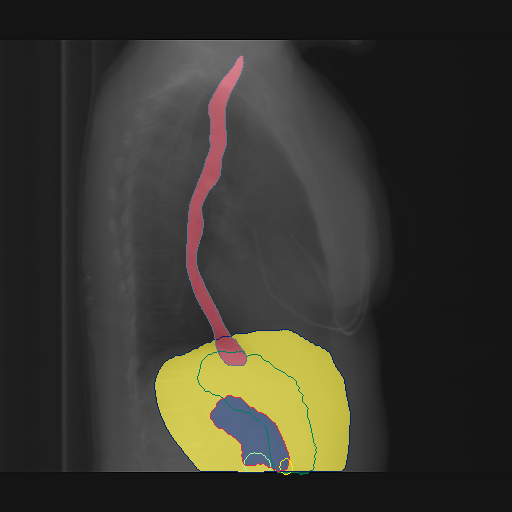

Automated Identification of the Center-Spine Distance via CXAS

We use all PA CXR from the MIMIC dataset and straightforwardly filter medical reports for the term scoliosis. We extract 2,054 images presenting scoliosis and 228,953 images not containing this phrase. We infer our CXAS model from all images and propose a spine-center distance (SCD) to measure the shift of the individual vertebrae. We calculate this by using the center point of the individual vertebrae segmentations. We then regress a centerline based on these vertebrae centers and compute the sum over the minimal distances of all vertebrae centers to the centerline.

To infer the difference in the SCD value between pathological and non-pathological cases, we conduct a t-test. Furthermore, to identify the diagnostic ability of this value, we display ROC curves for different subsets of the dataset according to sex.

In Fig. 4, we show qualitative examples of the calculation of the SCD for patients for the presence and absence of scoliosis. We can see that the vertebrae segmentation presents a noticeable curvature for the scoliosis case, leading to an SCD above 19, while for the patient with a healthy spine, the SCD is 1.125.

When conducting a t-test, we get a value of 35.30 (p-value 0.0001), indicating a statistically significant difference in SCD between positive and negative patients for scoliosis. On the left of Fig. 4, we show the distributions of the SCD in the form of violin plots for sex, age group, and pathology. Similarly to the CTR, SCD increases with age for the presence and absence of scoliosis. The results show that the older the patient gets, the less the disparity in mean SCD between scoliosis and no scoliosis becomes, indicating that the SCD becomes slightly less insightful the older the patient is. However, different from the CTR, the standard deviation of the SCD is considerably higher, and there is a relatively larger difference in means, leading to a higher predictive value for the identification of scoliosis.

On the right of Fig. 4, we show the ROC-Curve for pathology classification based on the SCD score. We see a difference in the diagnostic performance of the SCD for female and male patients with an AuROC of 0.77 and 0.80.